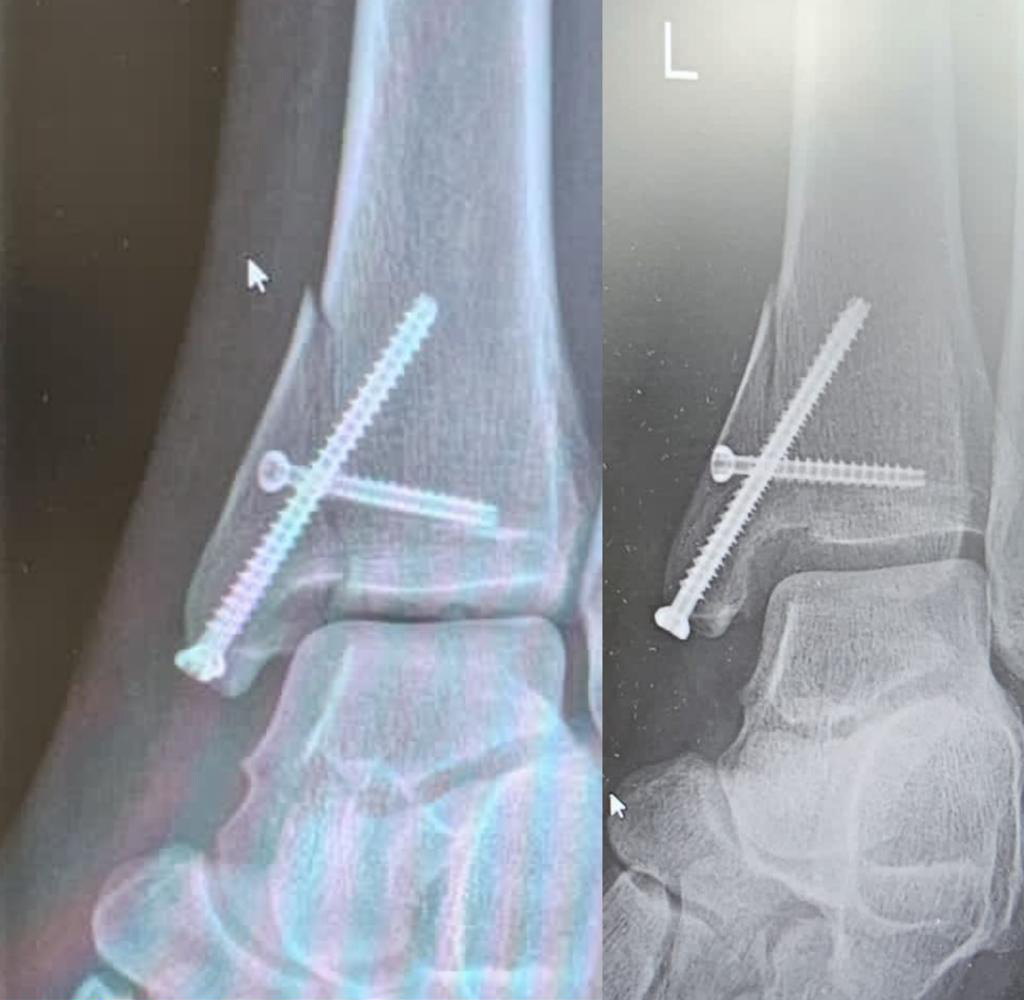

« À Jerez, j’ai réussi à rouler en moto, je ne me plains pas. Comme vous pouvez également le constater sur les radiographies, je me suis amélioré, mais je ne sais pas si je pourrai recommencer à tout faire comme dans ma première vie, plus dans la vie normale que dans le sport. Nous le savons tous : certaines fractures laissent des traces pendant des années et souvent toute une vie. Dès que le temps change un peu, qu’il fait un peu froid, que la douleur recommence à se faire sentir. Je sais faire de la physiothérapie, de la rééducation, tout le reste pour récupérer.”